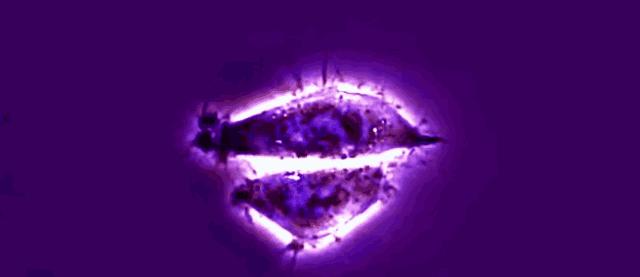

细胞分裂

电镜下的海拉细胞

但是,拉克斯的细胞生长趋势却让整个

研究室大呼意外,因为他们惊奇地发现

从拉克斯身体里取出的癌细胞具有

不可思议的复制速度,无论给海拉细胞

多大的空间,它都能迅速填满,它看

起来能永无止境地生长下去

人类历史上第一株永生的细胞就这样诞生了

海拉细胞增殖分裂

但海拉细胞的增殖速度比普通的癌细胞更快

海拉细胞不沦为普通细胞,在体外的培养

环境中也丝毫不影响它的繁殖与生长